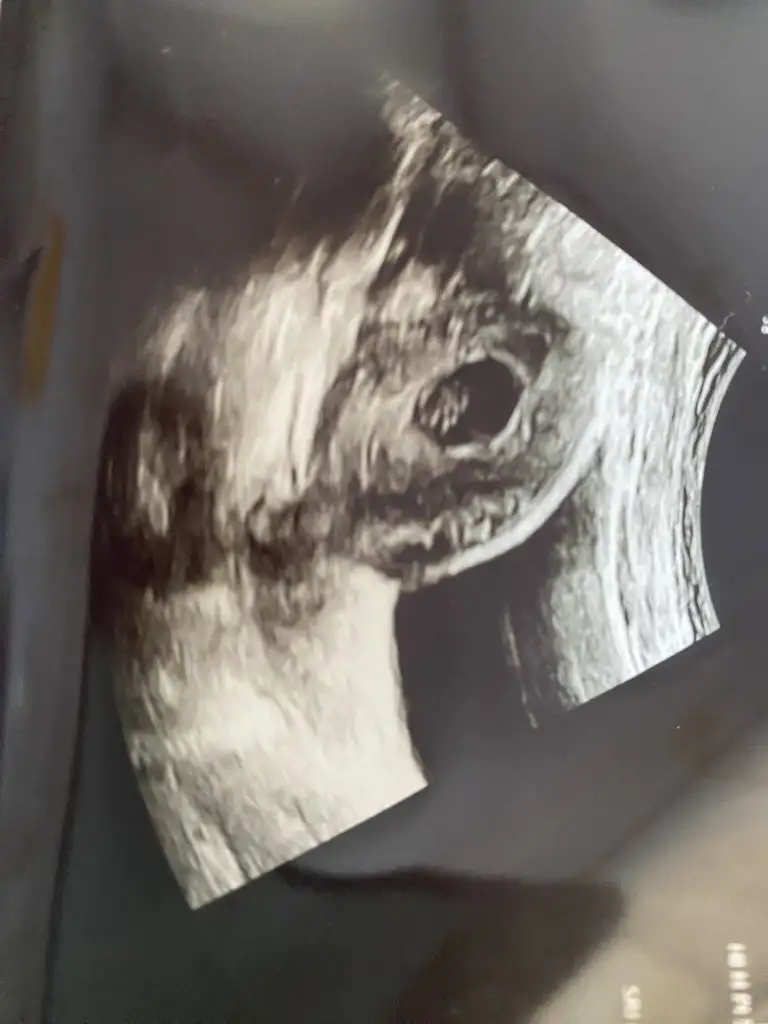

Merhaba bana da tahmin de bulunur musunuz? İlk bebeğim . Karından görüntü. Vajinal olan da var ama küçük orada :)Kız senin bebek bildigin yer degiştirmiş ya![]()

rica ediyorum bana da yorum yaparmısınız lütfenPlesentanın sagında solunda oluşuna göre yorum yapıyorum canım seninki tam ortada olabilir erkek genelde ortada duranlar da erkek oluyor saglıkla gelsin inşallah![]()